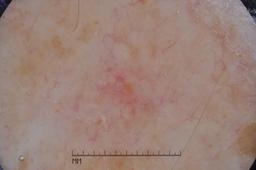

ISIC-DICM-17K (ISIC Dermoscopic Images and Clinical Metadata 17K) is a curated and balanced dataset derived from the International Skin Imaging Collaboration (ISIC) Archive Gallery. It comprises 17,060 dermoscopic images and clinical metadata (8,530 melanoma and 8,530 non-melanoma classes).

For more details, please follow the project’s GitHub repository: https://github.com/mmu-dermatology-research/isic-dicm-17k

This dataset was used in this study and benchmark to explore the effectiveness of multimodal learning for skin lesion classification:

S. Ahammed, X. Cui, W. Lu and M. H. Yap, "Skin Lesion Classification using Dermoscopic Images and Clinical Metadata: Insights from Multimodal Models," 2025 IEEE/CVF Conference on Computer Vision and Pattern Recognition Workshops (CVPRW), Nashville, TN, USA, 2025, pp. 222-230, DOI: 10.1109/CVPRW67362.2025.00027